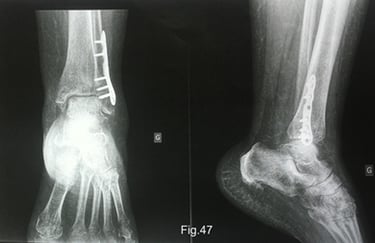

La radiographie montre que la fracture de la malléole externe est consolidée. Cependant, des signes d'ostéoporose pommelée (trabéculaire en forme de bulles) sont visibles dans le pied, c’est un signe typique de l’algodystrophie (Fig.47). Son chirurgien lui a prescrit une scintigraphie osseuse, avec un rendez-vous prévu dans dix jours. La scintigraphie osseuse permettra de confirmer le diagnostic d’algodystrophie.